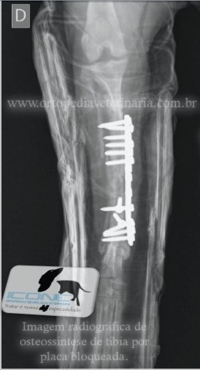

Placa Bloqueada consiste em um novo sistema de fixação interna onde a placa apresenta orifícios duplos, um liso para compressão e outro rosqueado para fixação do parafuso que se fixa a placa. Promove enorme estabilidade a fratura sendo possível associar parafusos neutros e compressivos.